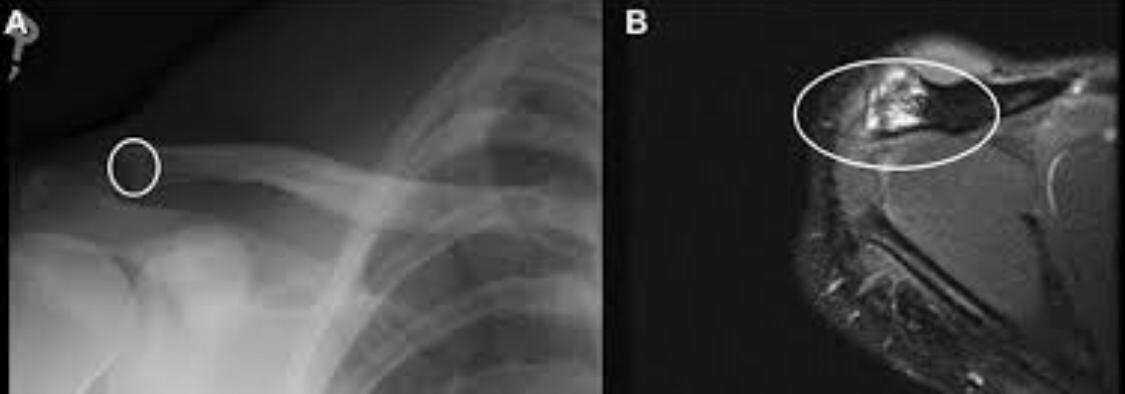

Distal clavicle osteolysis is a unique disease most likely due to an overuse phenomenon. Distal clavicular osteolysis (DCO) follows both chronic repetitive stress and single acromioclavicular trauma. Acute distal clavicular osteolysis was first described in 1936.

The exact aetiopathogenesis is unclear, but AC-joint trauma and subchondral microfractures seem to be involved. Subsequent attempts at repair are insufficient and the final result is osteolysis. It is unclear why changes predominate in the distal clavicle while the acromion is relatively spared.)

Mostly affected males in their 20s and commonly seen in weightlifters, symptoms usually begin with an insidious aching pain in the AC region that is exacerbated by weight training. Clinical findings are often nonspecific and frequently overlap with those of labral or rotator cuff tears. On examination, patients have point tenderness over the affected AC joint and pain with a cross-body adduction maneuver.

Conventional radiographs may remain normal during the first months or years. A 15° cephalad inclination avoids superposition of the scapular spine with the AC-joint (Zanca view).

Radiographic changes include cortical thinning, irregularity and microcysts in distal clavicle and mild AC–joint widening. A late finding is tapering of the distal clavicle.

MRI is far more sensitive to detect DCO in an early stage. The most common MR-finding is bone marrow oedema in the distal clavicle, sometimes also in the articular part of the acromion, but less distinct.

Often, a hypointense line is seen in this area of clavicular bone marrow oedema, representing a subchondral fracture. AC-joint abnormalities are common, and include effusion, mild widening, intra-articular bone fragments and capsule hypertrophy. Other MR-findings are similar to those seen on radiographs, as described above.

Bone scan may also shows increased uptake in the distal clavicle, which could be seen earlier than radiographic changes.

Treatment is essentially conservative, consisting of rest and nonsteroidal anti-inflammatory drugs (NSAID's), and is usually successful. In severe cases, resection of the distal clavicle is indicated. If left untreated, the process may cause progressive resorption of lateral aspect of the clavicle, erosions and cupping of the acromion and dystrophic calcifications.

DCO should be considered in the differential diagnosis of shoulder pain in the appropriate population. Therefore, analysis of MR arthrographic studies of the shoulder should not be restricted to evaluation of the rotator cuff and capsulolabral system, but the AC-joint should be scrutinised as well.